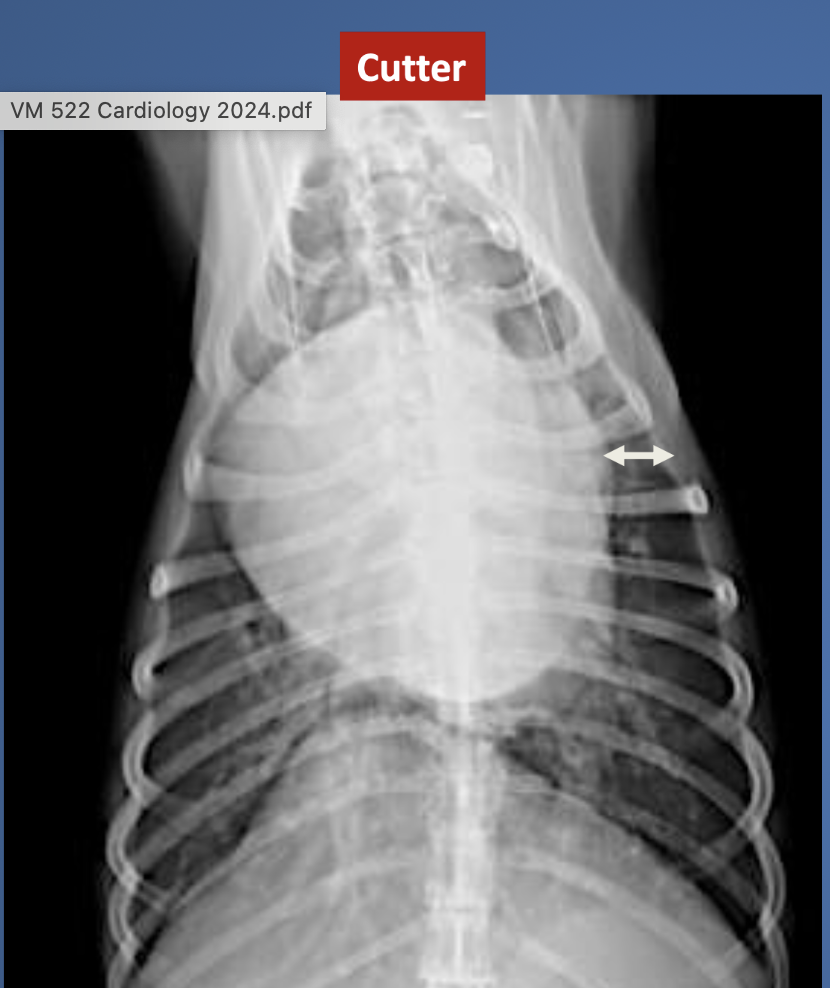

what is wrong with ? 12 YO Bichon mix with hx of frequent cough, esp. at night, high RR and HR, crackles on lung fields, left systolic HM, and many B lines on all lung fields with LA:Ao >2:1.

MVD. note the alveolar pattern (can see bronchi), LA enlarged, sternal contact, the enlarged heart vessels, and the raised trachea (other causes of raised trachea are PCE, mediastinal mass, pleural effusion).